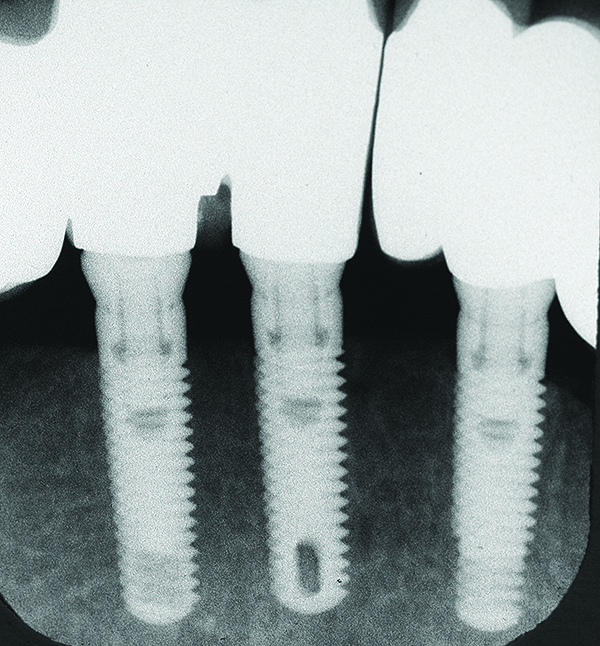

Fig 7 through Fig 14. Periapical radiographs of a 62-year-old woman who received a fixed porcelain-fused-to-metal reconstruction supported by abutments by internally connected dental implants. Fig 7 through Fig 10 are at initial prosthesis placement: mandibular site Nos. 30 and 29 (Fig 7); mandibular site Nos. 26, 25, and 23 (Fig 8); mandibular site Nos. 23 and 21 (Fig 9); mandibular site Nos. 21 through 19 (Fig 10). Fig 11 through Fig 14 are 11 years later (2013) and show excellent preservation of the vertical bone levels around the implants: mandibular site Nos. 30 and 29 (Fig 11); mandibular site Nos. 26 and 25 (Fig 12); mandibular site Nos. 25 and 23 (Fig 13); mandibular site Nos. 20 and 19 (Fig 14). It is interesting to note that in the mandibular right posterior quadrant there is a matched pair, ie, an external hex dental implant (No. 30) adjacent to an internally connected dental implant (No. 29). The bone levels around each of these designs are well-preserved at the 11-year follow-up.